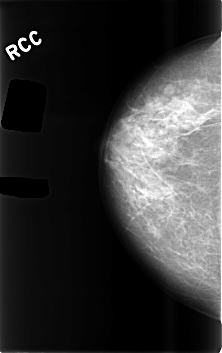

C_0491_1.RIGHT_CC

RIGHT_CC LINES 4584 PIXELS_PER_LINE 2880 BITS_PER_PIXEL 12 RESOLUTION 50 NON_OVERLAY